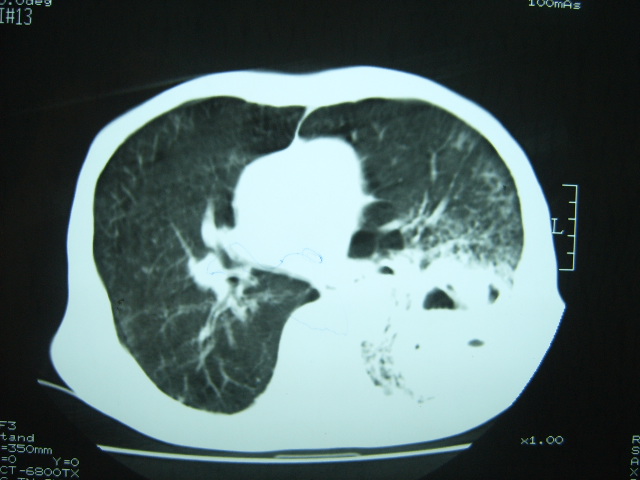

男74岁,咳嗽,寒战,低烧。有糖尿病史。

两肺结核,空洞形成,左下肺肺段隔离症待排

考虑:1、左下肺脓肿;

2、双肺结核。

考虑:糖尿病合并:1、左下肺炎继发肺脓肿;

考虑:1、左下肺脓肿;不排除霉菌感染

1、左下肺肺脓肿,合并霉菌球形成?.2、双肺陈旧性病灶.3、右上肺病灶警惕瘢痕癌,建议定期复查.

两肺结核,左下肺大片实变,内见空洞性病变,壁不规则,结合糖尿病史,考虑:结核性?霉菌性?建议结合实验室检查或治疗后复查。